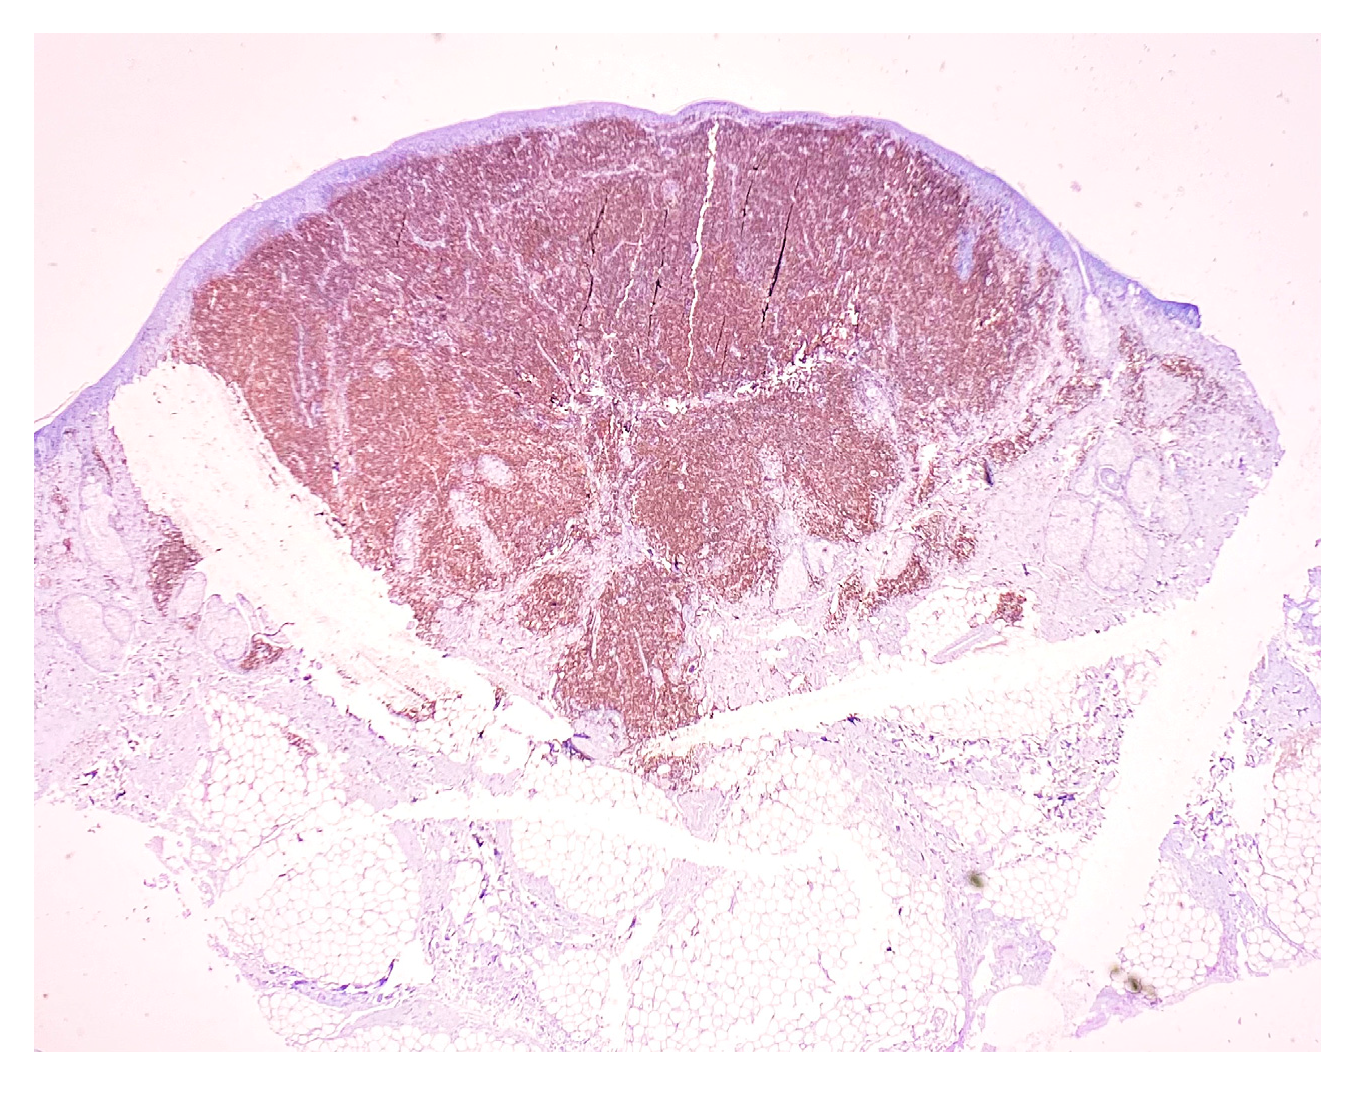

| Antibody | Clone | Producer | Pretreatment | Dilution |

|---|---|---|---|---|

| CD3 | MRQ-39 | Cell Marque | HIER EDTA 19 min | 1:100 |

| CD4 | EP204 | Cell Marque | HIER EDTA 19 min | 1:200 |

| CD8 | C8/144B | Cell Marque | HIER EDTA 19 min | 1:200 |

| CD20 | L26 | Cell Marque | HIER EDTA 19 min | 1:100 |

| CD30 | Ber-H2 | Bio SB | HIER EDTA 19 min | 1:100 |

| Ki67 | MIB-1 | DAKO | HIER EDTA 19 min | 1:200 |

| PD1 | NAT105 | Cell Marque | HIER EDTA 19 min | 1:100 |